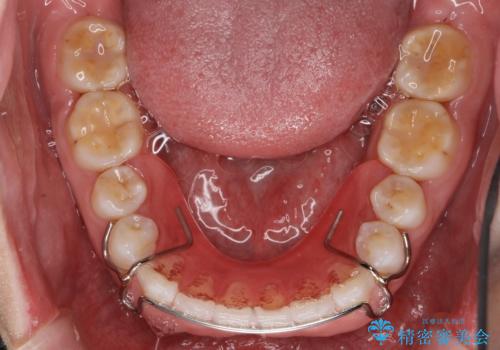

プレートタイプの保定装置について

当院では日中に使っていただく審美性に優れたマウスピースタイプの保定装置とは別に、プレートタイプの保定装置をお作りするすることもできます。

プレートタイプの保定装置は清掃性が高く、臼歯離開(上下の奥歯どうしに隙間ができる症状)等、咬み合わせの問題が生じにくいのが特徴です。